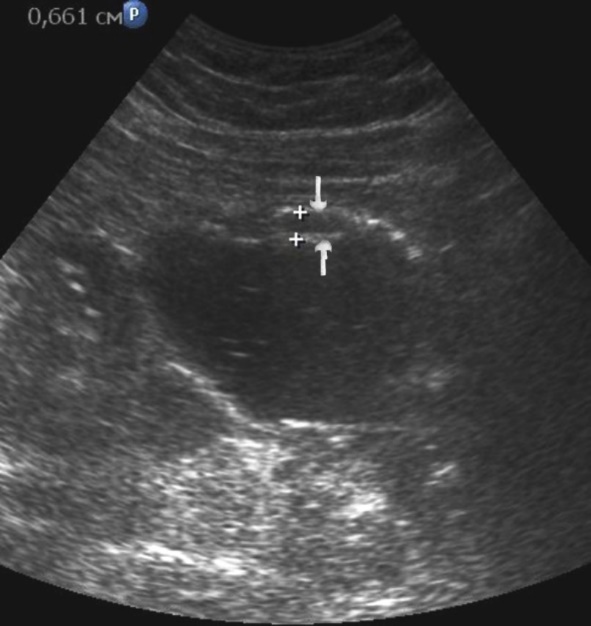

Distal gastric cancer was observed in 24 (39,3%) cases and contributed to the development of pyloric stenosis: in 6 (9,8%) cases it was compensated, in 18 (29,5%) – was sub compensated. The layers of the wall were not differentiated in all patients with sub compensated pyloric stenosis. In the case of compensated pyloric stenosis, the thickness of the affected area was 10,2±2,9mm, the length was 27,1±6,2mm, the diameter of the pylorus was 8,3±0,8mm (Figure 14). Among patients with sub compensated pyloric stenosis, the thickness of the stomach wall was 19,8±4,1mm, the length was 43,6±4,5mm, the pyloric diameter was 4,3±1,1mm (Figure 15).

Figure 14.Gastric carcinomas of diffuse infiltrative form in the atrium of T2 stage. Compensated pyloric stenos. On an empty stomach in the cavity of the stomach is determined an a small amount of fluid. The diameter of the pyloric canal more than 7 mm.

Figure 15.Distal gastric carcinomas of diffuse infiltrative form of T3 stage. Sub compensated pyloric stenos (arrows). The thickness of the anterior wall of the stomach is 9,13 mm, extent of the affected area – 7,84 cm. On an empty stomach in the cavity of the stomach is determined an a large amount of fluid. The diameter of the pyloric canal is about 6 mm.